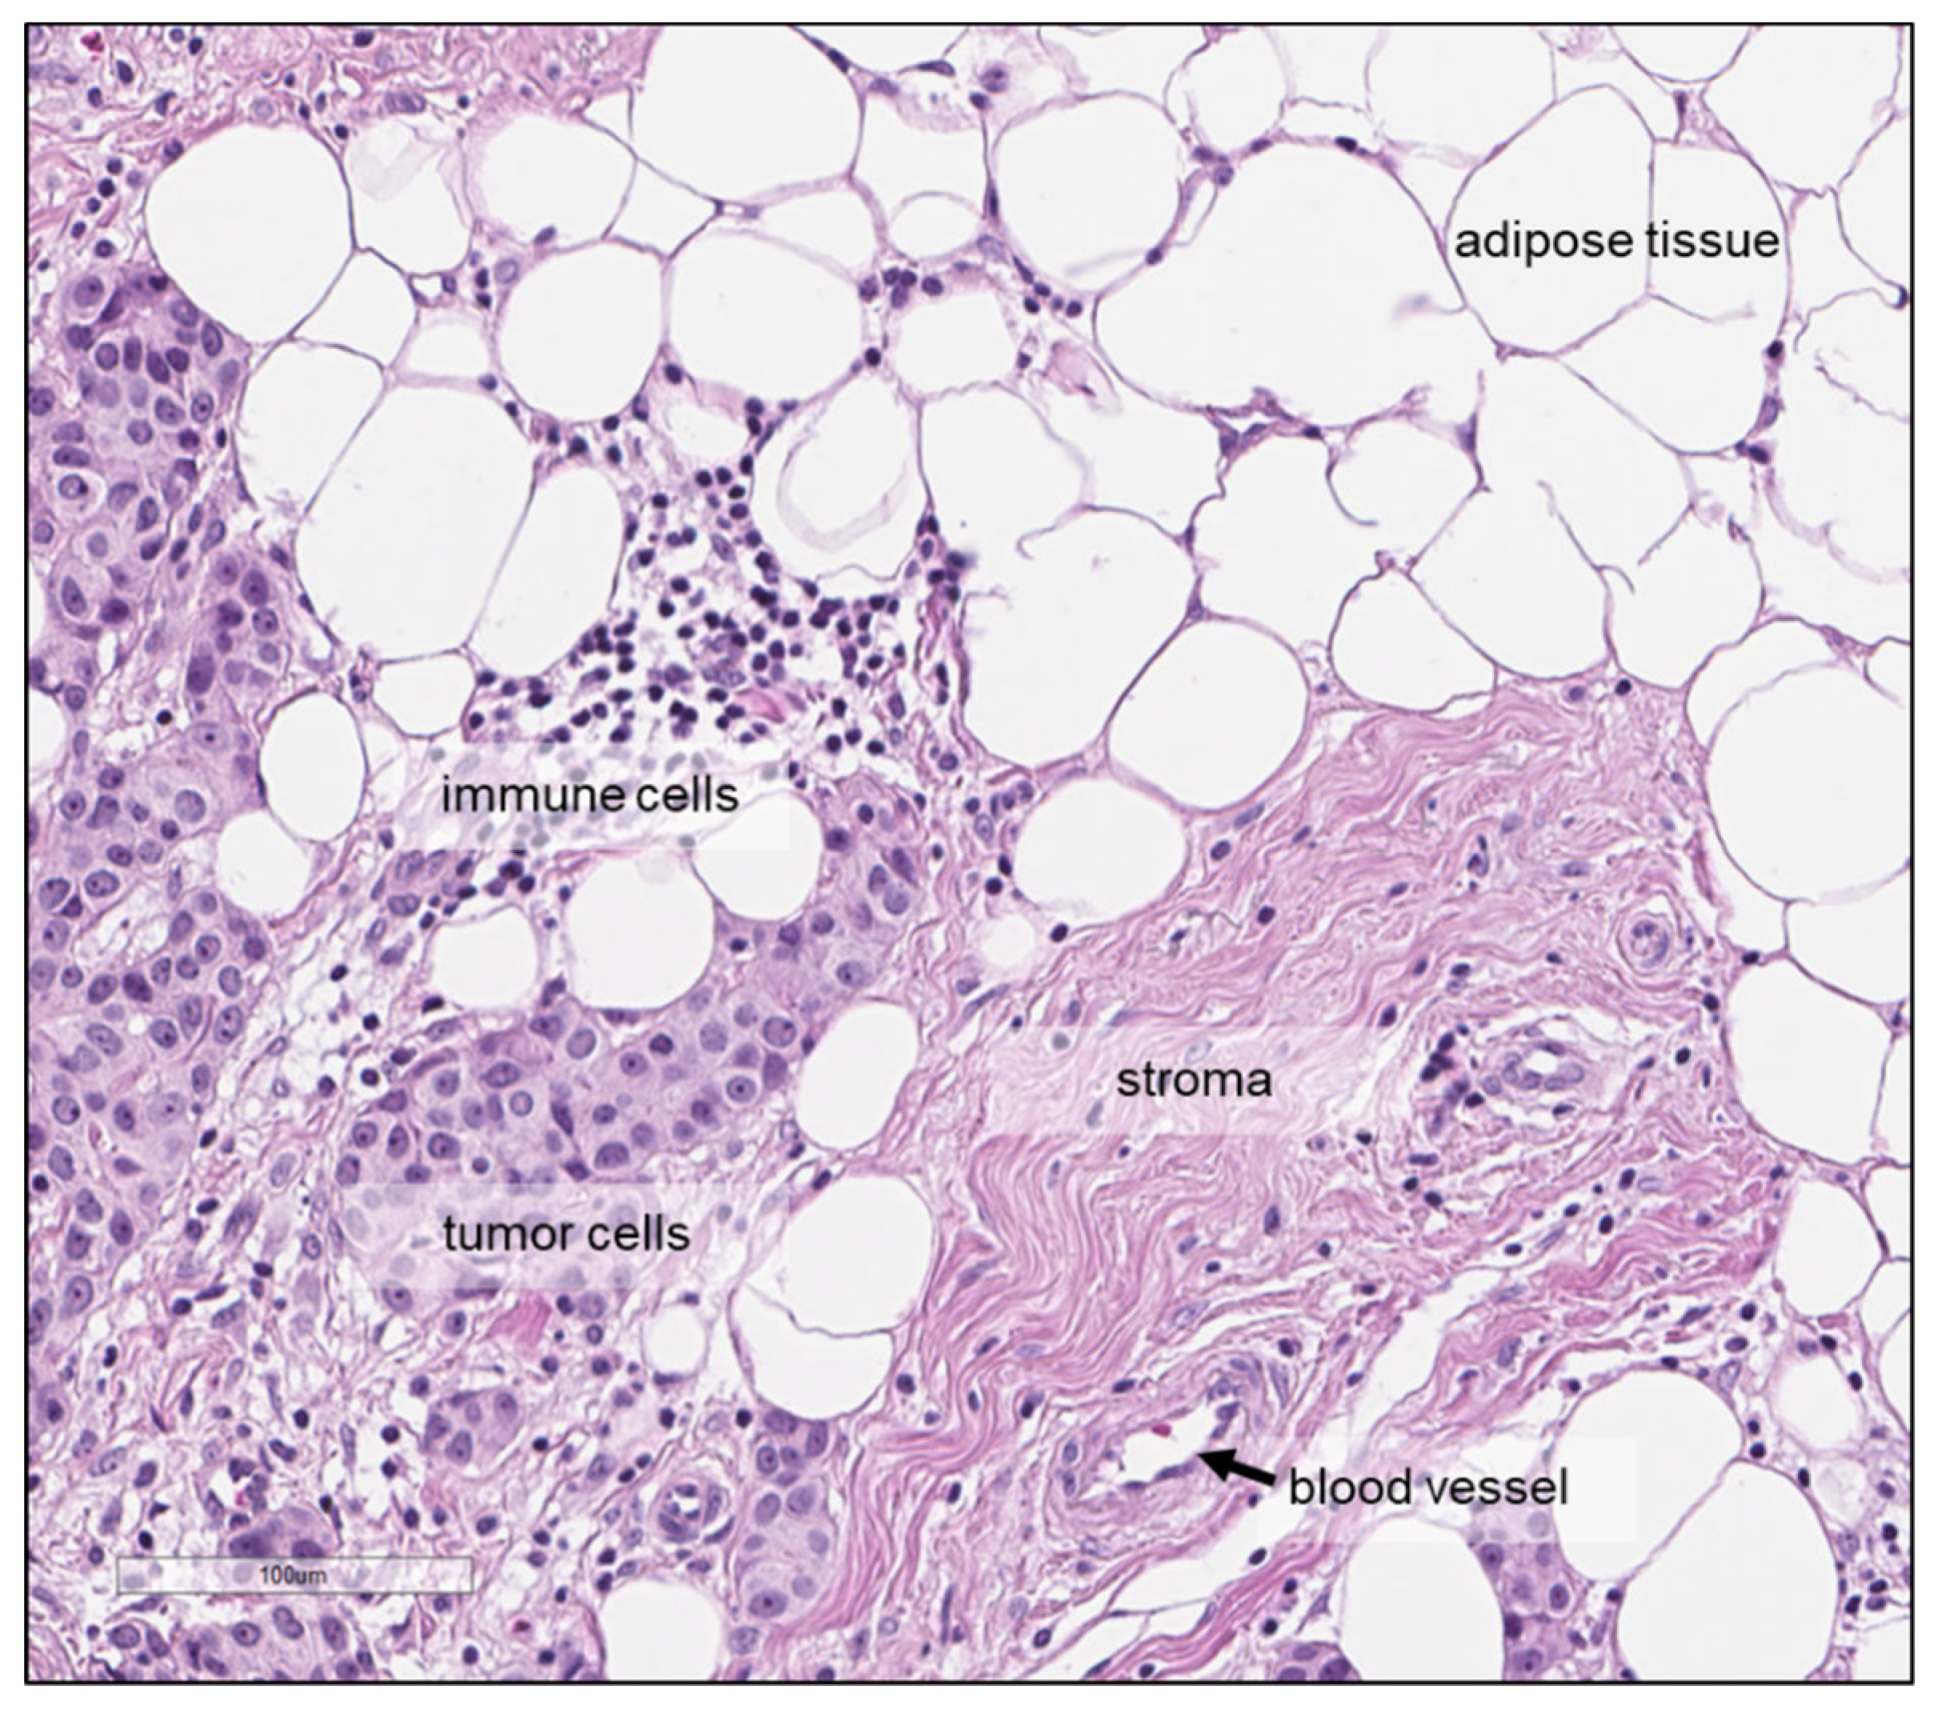

- Gogiashvili, M.; Horsch, S.; Marchan, R.; Gianmoena, K.; Cadenas, C.; Tanner, B.; Naumann, S.; Ersova, D.; Lippek, F.; Rahnenführer, J.; et al. Impact of intratumoral heterogeneity of breast cancer tissue on quantitative metabolomics using high-resolution magic angle spinning 1 H NMR spectroscopy. NMR Biomed. 2018, 31. [Google Scholar] [CrossRef] [PubMed]